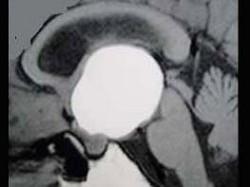

问题 女,38岁,闭经、嗜睡、尿多、视物模糊半年,精神烦躁,CT、MRI检查如图,最可能的诊断为()

选项 A.颅咽管瘤 B.脑膜瘤 C.蛛网膜囊肿 D.垂体瘤 E.表皮样囊肿

答案 A